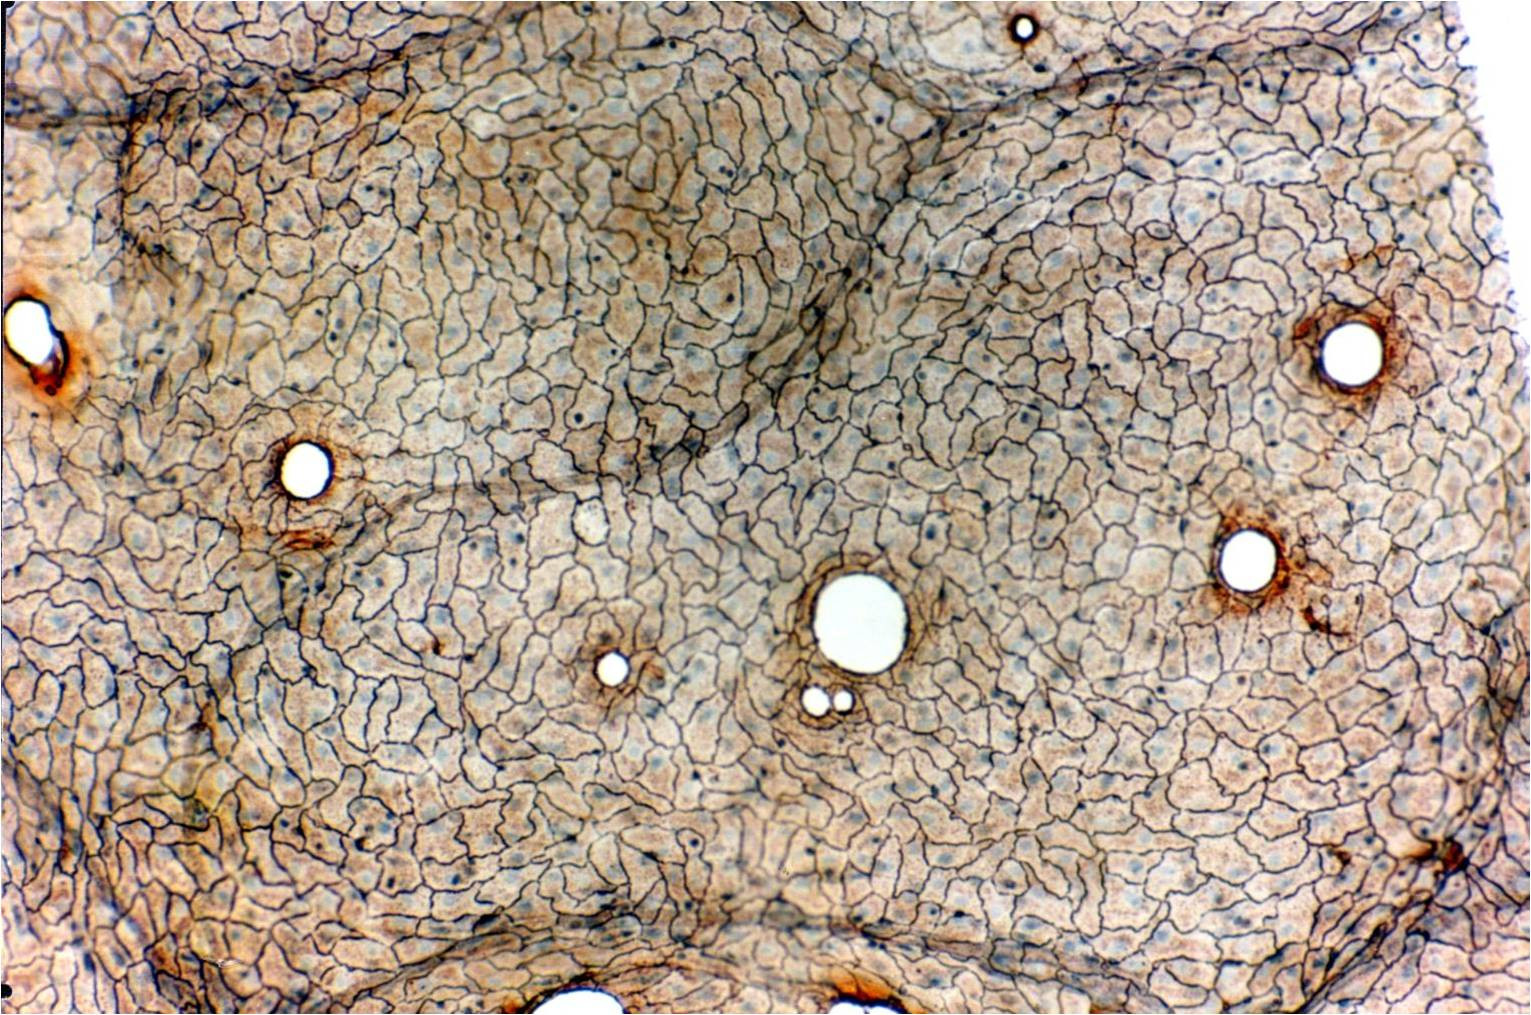

2. 单层扁平上皮结构.jpg